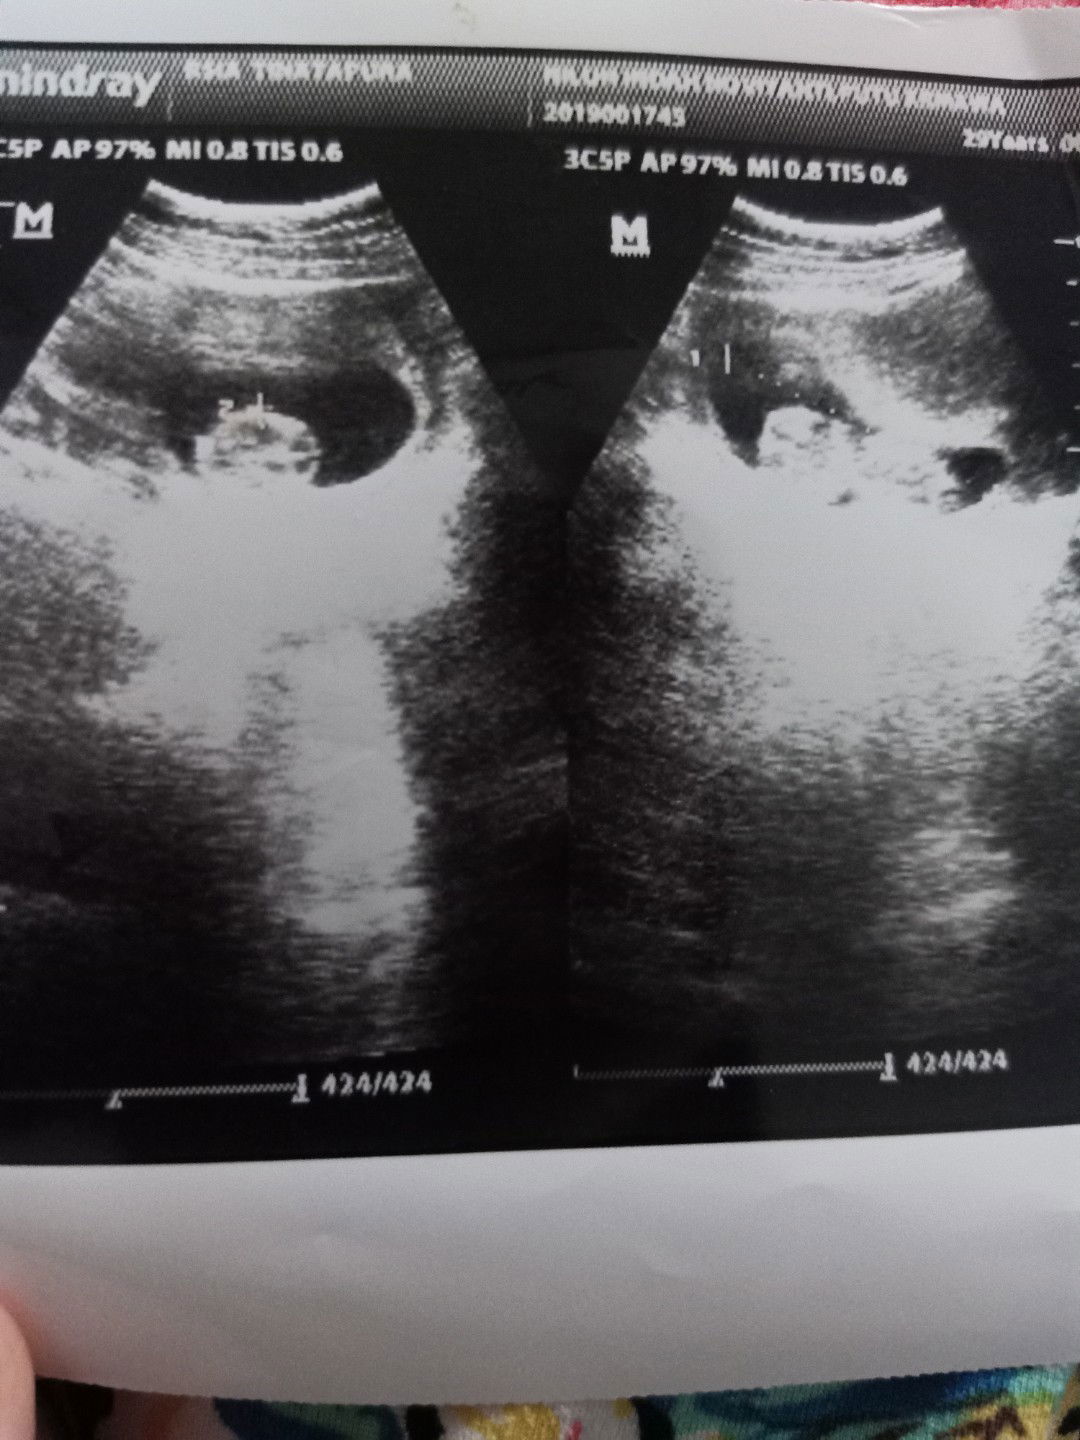

Hay Bun... in hasil USG kemarin. mau tau donk lagi apa yaaa dia sekarang???

Lagi apa yaa dia sekarang